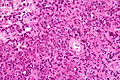

| Glioblastoma (WHO grade IV) | glial processes (esp. on smear), nuclear atypia (typical size var. ~3x, irreg. nuc. membrane, hyperchromasia), no Rosenthal fibres in the core of the lesion †, microvascular proliferation or necrosis | often enhancing (suggests high grade), usu. supratentorial, usu. white matter | usu. old, occ. young | very common, esp. glioblastoma | IDH-1+/-, GFAP+ | |

Images

Anaplastic astrocytoma: